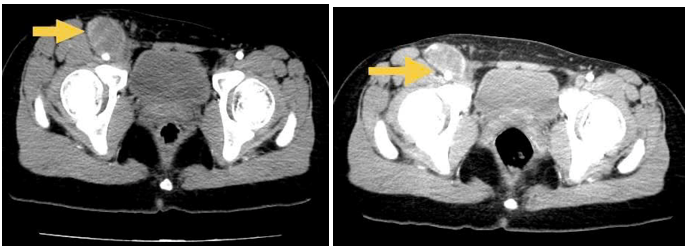

- CT ổ bụng có tiêm thuốc cản quang : Gan: Kích thước bình thường, bờ đều. Nhu mô hạ phân thuỳ IV có ổ ngấm thuốc kém kích thước ~ 25x7mm.

Hình 1: Nhu mô gan hạ phân thuỳ IV có ổ ngấm thuốc kém kích thước ~ 25x7mm. ( mũi tên vàng)